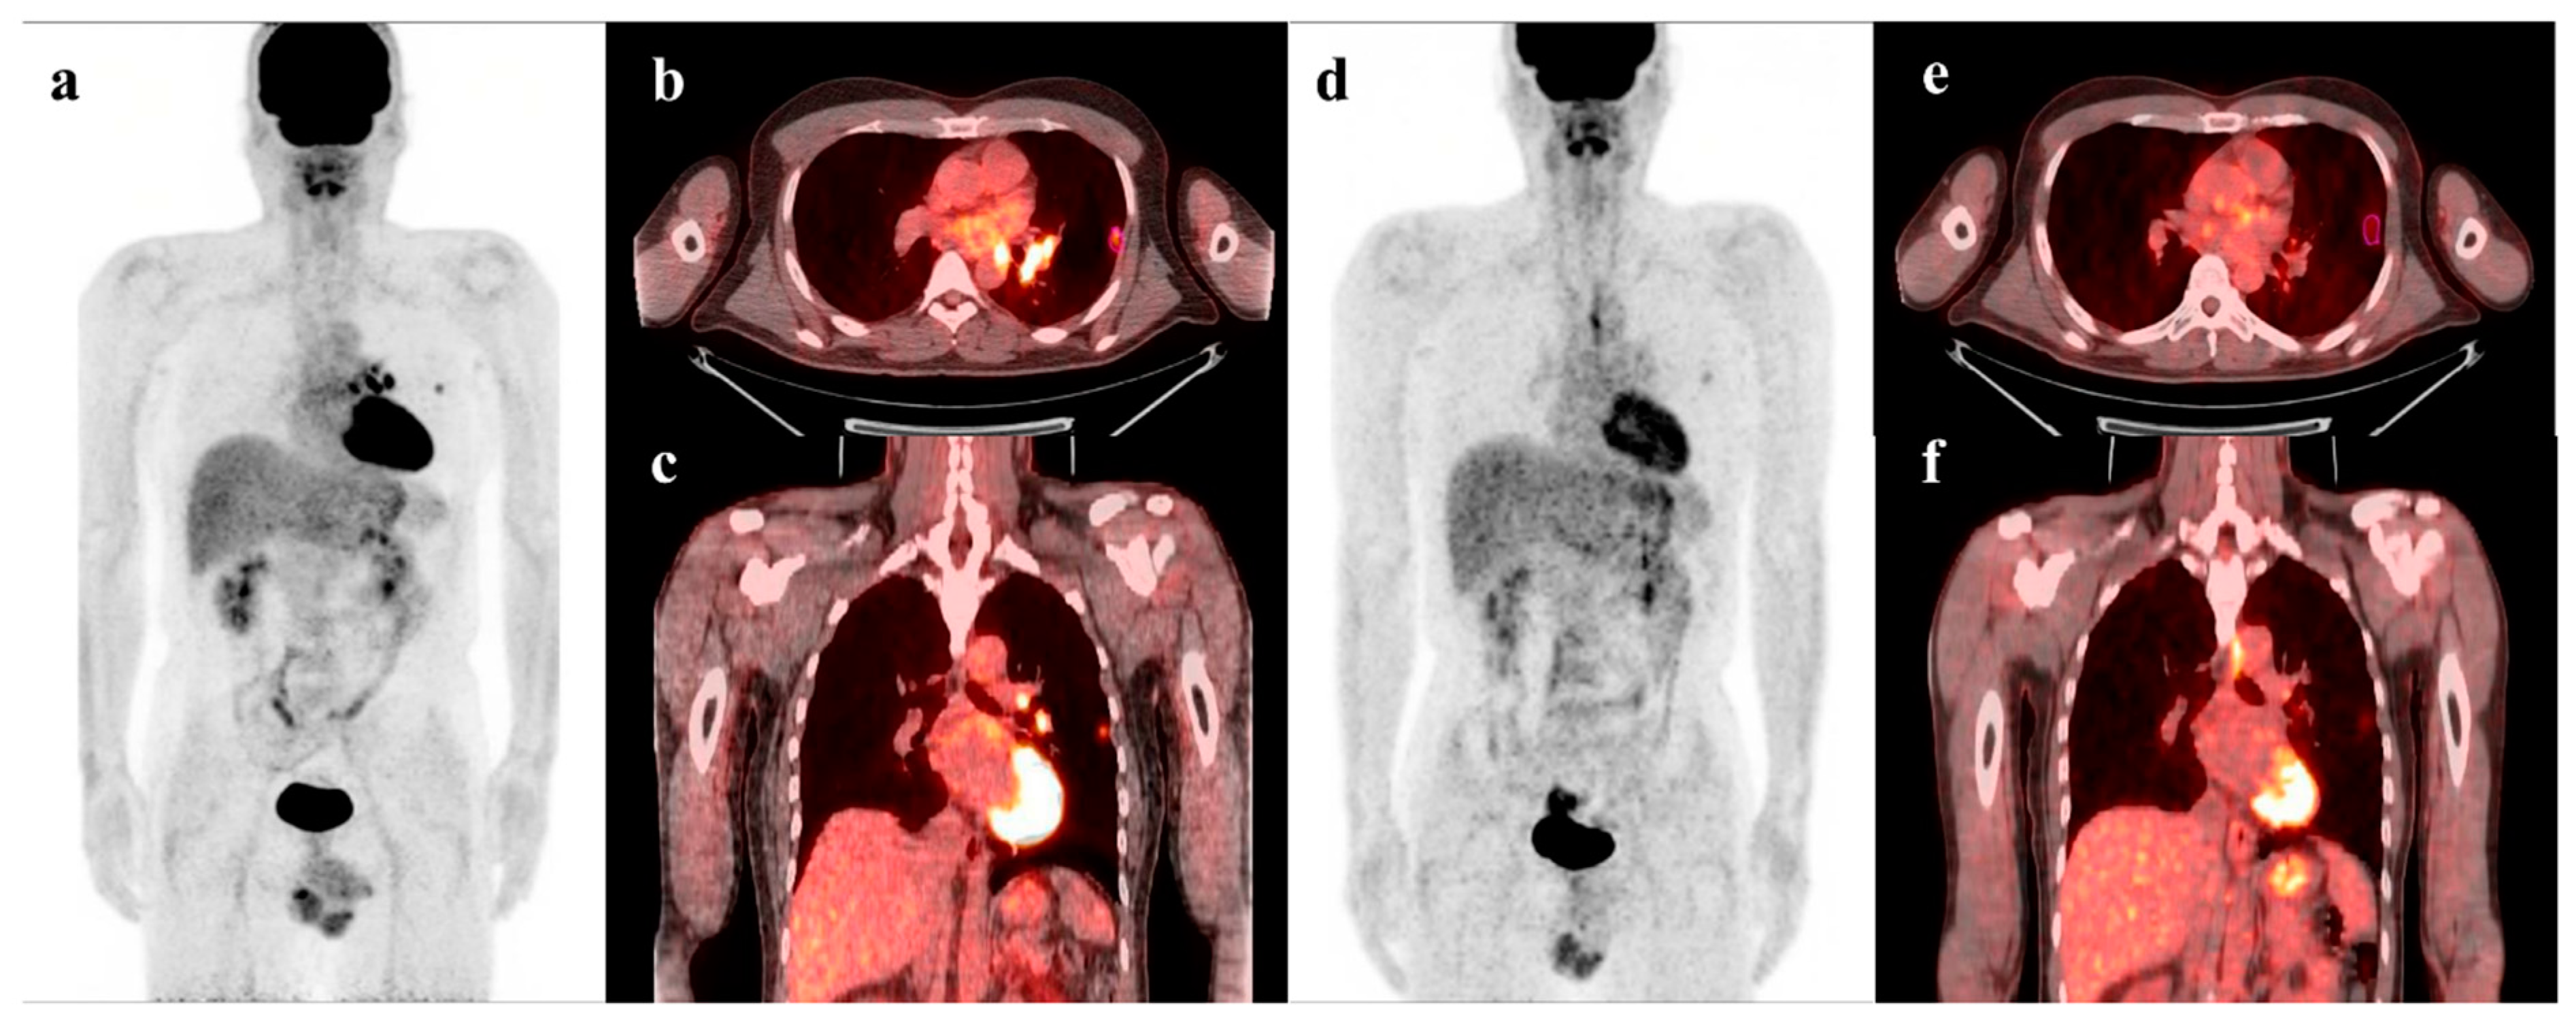

2.2. 18F-FDG PET/CT Acquisition and Analysis

- Yoo, J.; Lee, J.; Cheon, M.; Woo, S.-K.; Ahn, M.-J.; Pyo, H.R.; Choi, Y.S.; Han, J.H.; Choi, J.Y. Predictive Value of 18F-FDG PET/CT Using Machine Learning for Pathological Response to Neoadjuvant Concurrent Chemoradiotherapy in Patients with Stage III Non-Small Cell Lung Cancer. Cancers 2022, 14, 1987. [Google Scholar] [CrossRef]